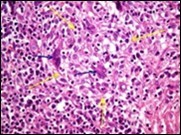

Core needle biopsy of idiopathic granulomatous mastitis enunciates multiple aggregates of non- caseating epitheloid cell granulomas within and encompassing breast lobules, constituted of epitheloid histiocytes, lymphocytes, neutrophils and multinucleated giant cells. Granulomatous inflammation is predominantly lobulo-centric. The inflammation is preponderantly composed of lymphocytes, plasma cells, epitheloid histiocytes, multinucleated giant cells and neutrophils. Neutrophils can configure micro-abscesses and encompass vacant micro-cystic cavities, morphological features which are in common with cystic neutrophilic granulomatous mastitis. Non specific lobulitis along with a lymphoid and plasma cell infiltrate accompanies the granulomatous inflammation. Necrosis is usually absent. Neutrophilic micro-abscesses can be accompanied by fistula formation 4, 5.

Fine needle aspiration can demonstrate a cellular exudate indicative of an abscess with an intense inflammatory infiltrate preponderantly composed of neutrophils. Ductal epithelial cells may be absent. Cytological examination delineates abundant and accumulated epitheloid histiocytes, neutrophils, lymphocytes with a variable degree of granuloma formation and an absence of necrosis 5.

Figure 7.Granulomatous mastitis with scattered epitheloid cells, neutrophilic exudate and aggregates of epithelod cells15.

Figure 8.Granulomatous mastitis with disseminated epitheloid cells admixed with neutrophils, lymphocytes and plasma cells 16.

Figure 9.Granulomatous mastitis with circumscribed epitheloid cell granuloma, foreign body giant cells and a perimeter of lymphocytes 17.

Figure 10.Granulomatous mastitis with a ductal circumscription of epitheloid cells, plasma cells, lymphocytes and neutrophils 18.